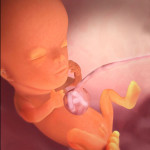

Voici à quoi ressemble le fœtus à la semaine 11 (cliquable):

L'enfant entier a maintenant la taille de la chaux. La longueur du corps est de 44 à 60 mm et le poids est d'environ 8 g.

Tous les organes et systèmes de l'enfant sont déjà formés. Ils sont dans un état différent. Par exemple, un petit cœur bat longtemps et complètement. Mais il n'y a pas encore de squelette, le tissu osseux reste au stade cartilagineux. Jusqu'à présent, seuls les globules rouges (globules rouges) sont contenus dans le sang et les globules blancs se forment plus tard. Mais les cordes vocales se sont presque développées, bien que le bébé n'en aura pas besoin bientôt.

À la 11e semaine, ils développent activement:

- tractus intestinal;

- foie (il «occupe» 10% du poids du fœtus entier);

- muscles du cou et de la poitrine;

- iris des yeux;

- vaisseaux sanguins;

- poumons, bronches et trachée;

- tendons;

- les membranes disparaissent sur les orteils;

- un motif de peau individuel apparaît sur le bout des doigts;

- un réflexe de saisie commence son développement;

- la formation des rudiments des dents primaires se poursuit.

À l'heure actuelle, le bébé commence généralement à bouger la tête.